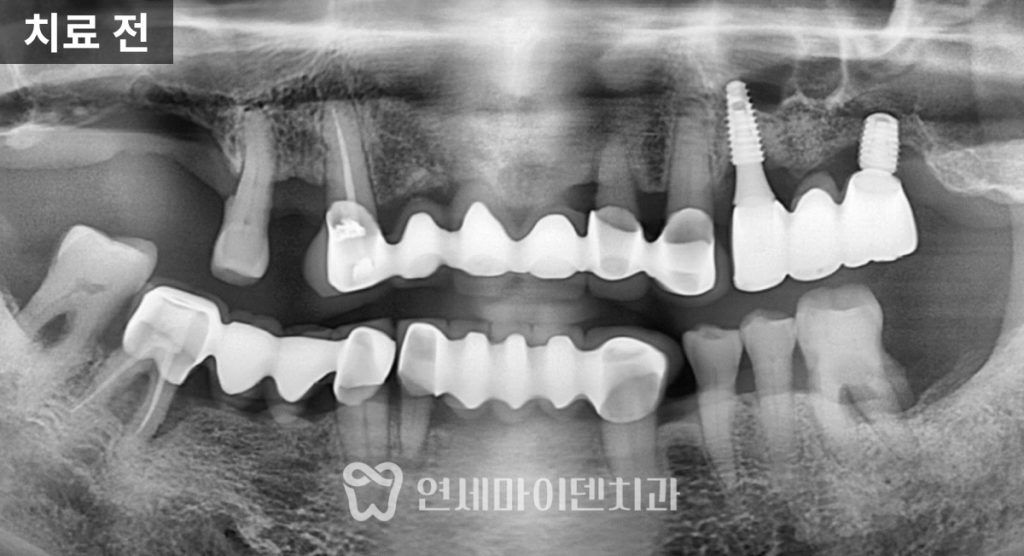

검사 결과, 위쪽 어금니 부위에는

과거 두 개의 임플란트를 연결한

임플란트 브릿지가 사용되고 있었고,

특히 뒤쪽 임플란트는 뿌리 끝까지

뼈 소실이 매우 심한 상태였습니다.

이 정도라면 보존적으로 끌고 가기보다는

제거가 불가피한 상황이었습니다.